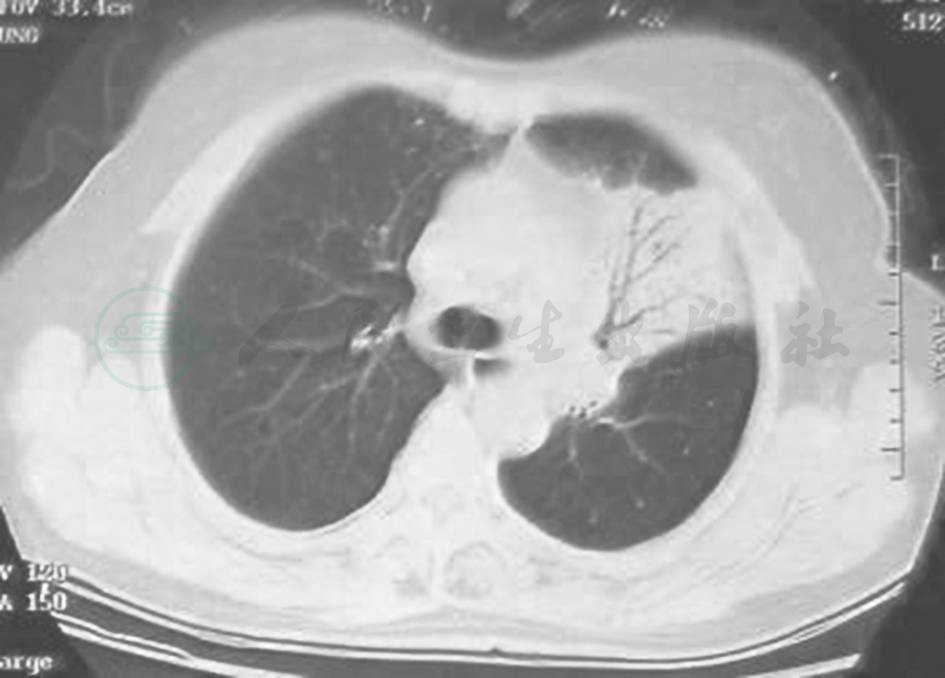

确诊后,于2010年11月25日开始予以R-CHOP方案化疗(利妥昔单抗600mg,化疗前1天;环磷酰胺0.8g,表柔比星80mg,长春地辛4mg,化疗第1天;泼尼松80mg,化疗第1~5天)。化疗3个疗程后复查胸部CT,提示肺内病变吸收不明显(图5);改为FND方案(氟达拉滨40mg,第1~3天;米托恩醌8mg,第1天;地塞米松20mg,第1~5天)化疗3个疗程,患者无明显不适主诉,胸部CT示左上肺病变较前吸收(图6)。

图6 复查胸部CT表现(2011-08)

胸部CT显示,与2011年1月比较,左肺实变影较前明显吸收,但肺内囊泡影较前增大